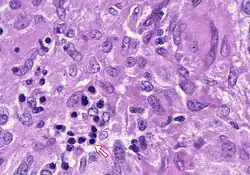

Councilman body (upper-right) and ballooning degeneration (centre-left). H&E stain.

In pathology, a Councilman body, also known as a Councilman hyaline body or apoptotic body, is an eosinophilic globule of apoptotic hepatocyte cell fragments. Ultimately, the fragments are taken up by macrophages or adjacent parenchymal cells.[1] They are found in the liver of individuals suffering from acute viral hepatitis, yellow fever, and other viral syndromes.[2]

With a bright field microscope, Councilman described typical, discrete, necrotic lesions in human hepatic cells of those infected with yellow fever.[9] He noted that the bodies appeared to be red in hematoxylin and eosin-stained sections of hepatic tissue, while being circumscribed, varying in size, round or irregular shape, and having numerous vacuoles of different sizes.